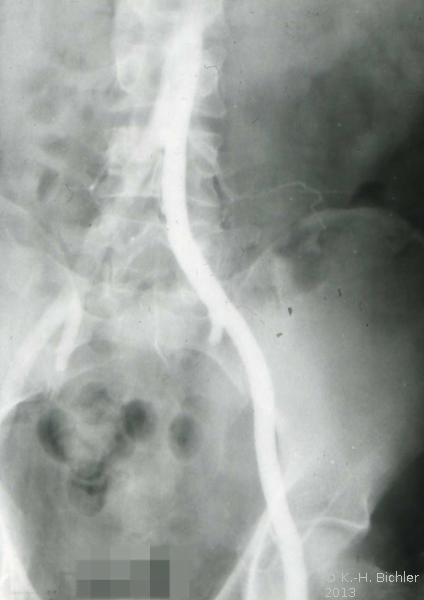

Vaskulär verursachte Abstoßungen können neben immunologisch bedingter Arterienstenose auch nahttechnisch verursacht sein. Angiodynographische bzw. angiographische Abklärung ist erforderlich, evtl. anschließende Angioplastie. Die Angiodynographie stellt ein wichtiges diagnostisches Verfahren zum Nachweis der Durchblutung des Organs im postoperativen Verlauf dar (Abbildung 9).

Zur Gefäßdarstellung ist die Angiographie und eventuell Dilatation der Arterie induziert.

Die Abbildung 10 zeigt den Gefäßabbruch der Art. hypogastrica links bei Abstosungsreaktion der implantierten Niere und die Abbildung 11 das explantierte Organ

Literatur:Spinosa, D. J. et al: "Angiographic evaluation and treatment of transplant renal artery stenosis", Curr. Op Urol. 11, 197-205, 2001.